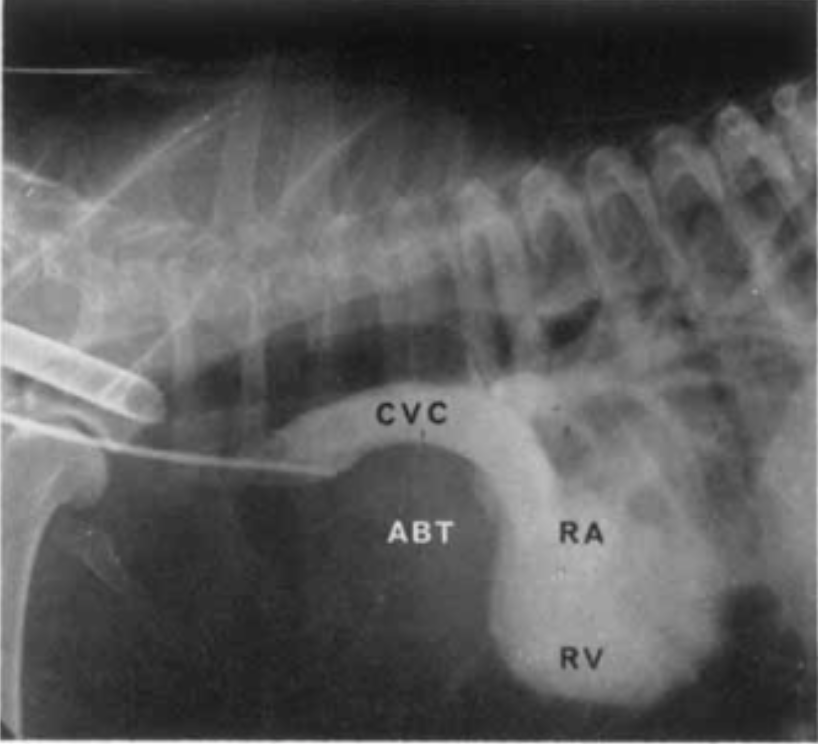

Selective angiography - right atrial injection (normmal dog)

A

RAA = right auricular appendage

RV = right ventricle

PSV = pulmonary sinus of valsalva

MPA = main pulmonary artery

RPA = right pulmonary artery

LPA = left pulmonary artery

Cranial vena caval injection angiogram (dog)

What are the pertinent findings and diagnosis?